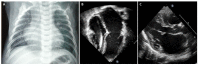

Restrictive cardiomyopathy (RCM) is characterized by restrictive ventricular pathophysiology determined by increased myocardial stiffness. While suspicion of RCM is initially raised by clinical evaluation and supported by electrocardiographic and echocardiographic findings, invasive hemodynamic evaluation is often required for diagnosis and management of patients during follow-up. RCM is commonly associated with a poor prognosis and a high incidence of heart failure, and PH is reported in paediatric patients with RCM. Currently, only a few therapies are available for specific RCM aetiologies. Early referral to centres for advanced heart failure treatment is often necessary. The aim of this review is to address questions frequently asked when facing paediatric patients with RCM, including issues related to aetiologies, clinical presentation, diagnostic process and prognosis.